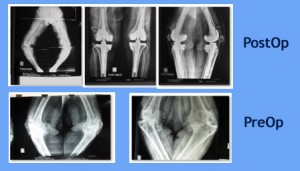

61 years female. Rheumatoid. Bilateral Total Knee Replacement 4 yrs ago. Fell down 6 months post surgery and injured left knee.

Since then global instability in left knee and inability to walk.

X-ray left knee AP and lateral shows subluxation with fixed implant.

Revision TKR done with RHK (Rotating Hinge Knee) to substitute ... Read more..